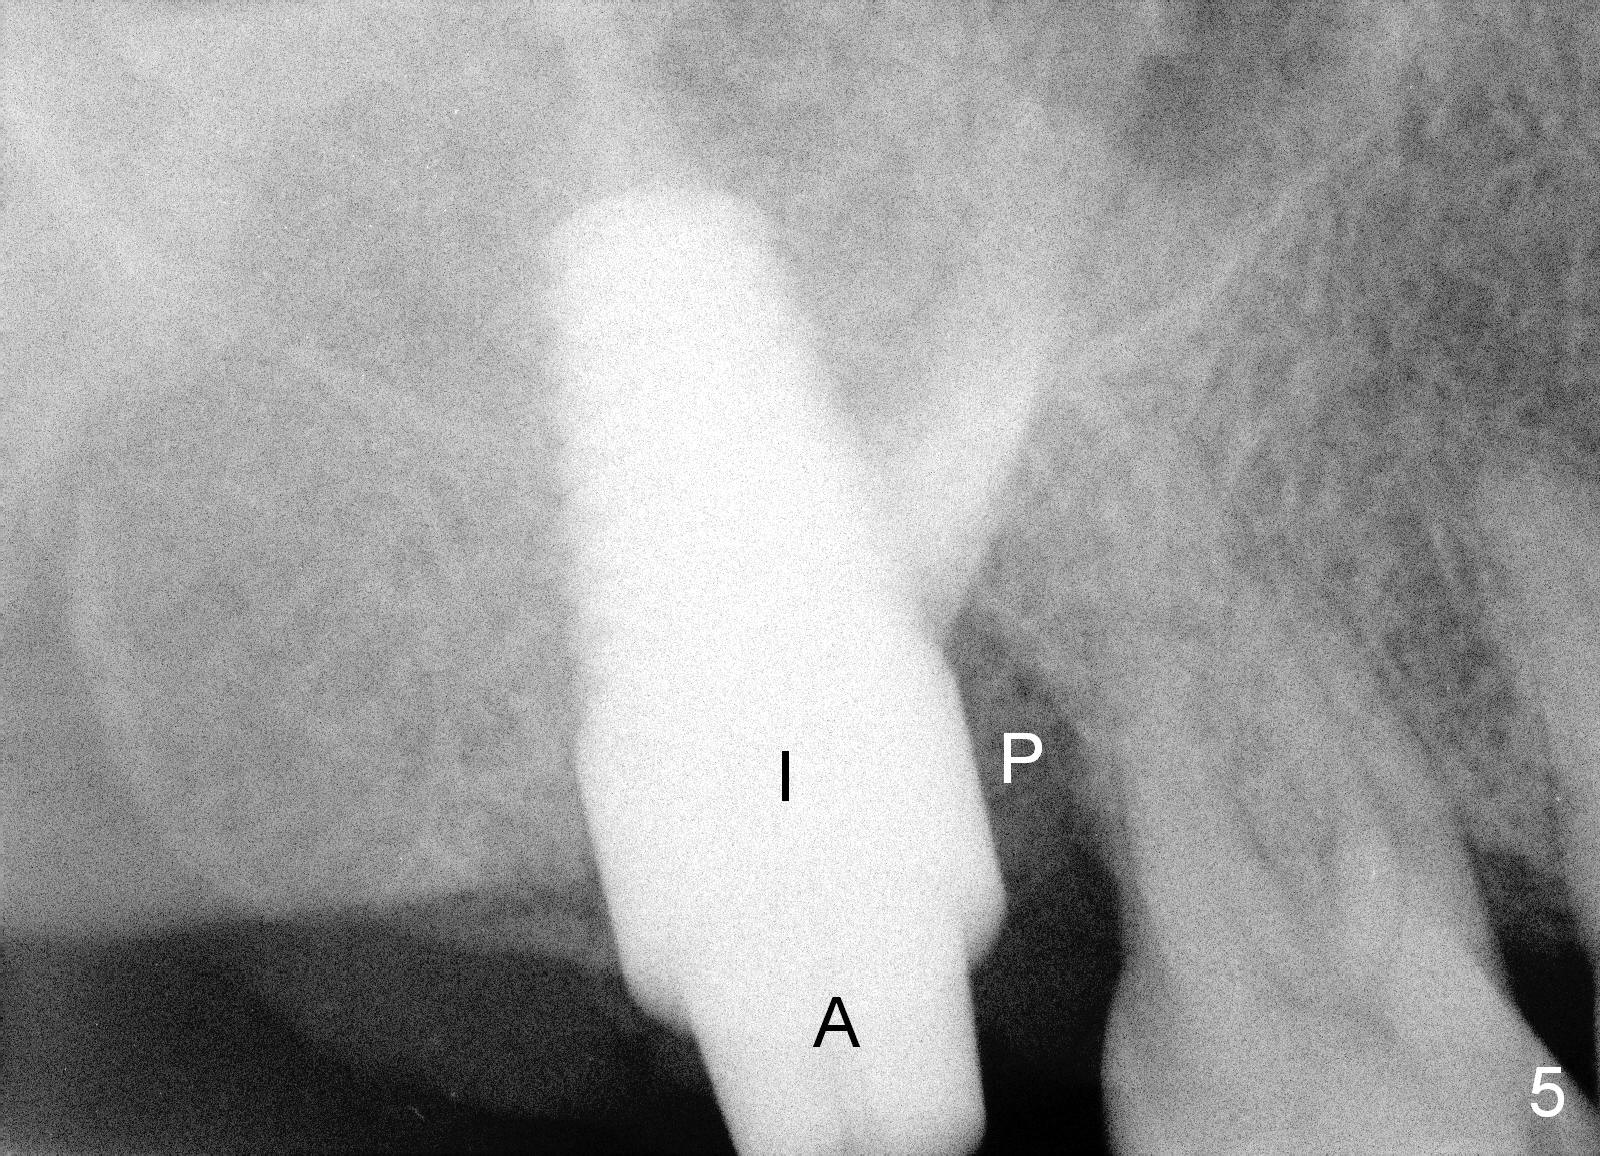

When she returns 7 years later, the tooth #2 has perio abscess with severe bone loss (Fig.3). She refuses to take antibiotic for infection control, but agrees to have immediate implant for #2 because of 1-staged surgery (Fig.5 I: 8x17 mm; A: abutment; P: bone powder (graft)). She is aware of delayed implants at the sites of #15 and 31 later. The bone height at the site of #15 reduces from 12 mm (Fig.4) to 7 mm (Fig.6) in 7 years.

The large implant obliterates the socket mesiodistally (Fig.7); the buccal (B) and palatal (P) gaps are filled with bone graft, which is held in place by an immediate provisional.

The tissue-level implant is placed subgingivally (mesially); insertion torque is 15 Ncm. The same diameter cylindrical implant with larger surface area may achieve higher insertion torque with supragingival margin. The latter is easy for restoration.